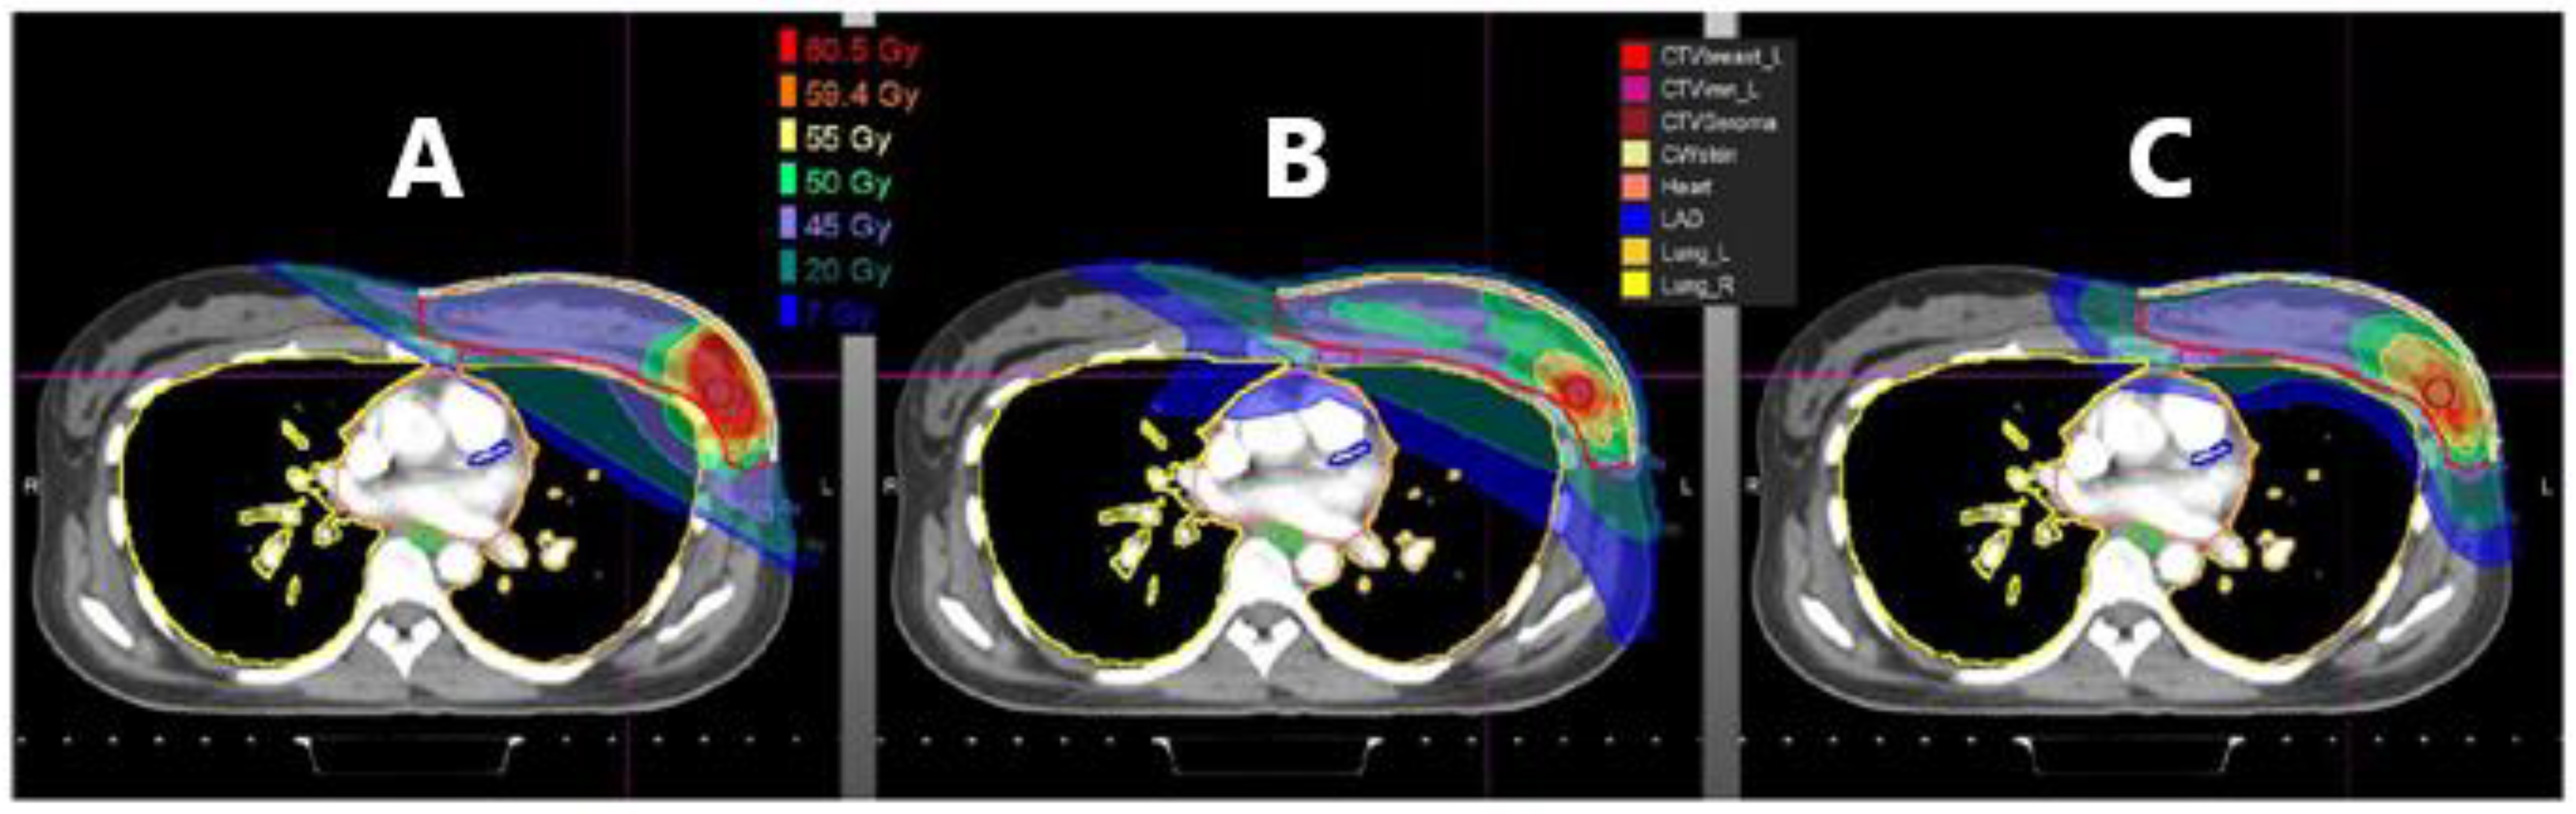

- Mutter, R.W.; Choi, J.I.; Jimenez, R.B.; Kirova, Y.M.; Fagundes, M.; Haffty, B.G.; Amos, R.A.; Bradley, J.A.; Chen, P.Y.; Ding, X.; et al. Proton Therapy for Breast Cancer: A Consensus Statement From the Particle Therapy Cooperative Group Breast Cancer Subcommittee. IJROBP 2021, 111, 337–359. [Google Scholar] [CrossRef]

- Depauw, N.; Batin, E.; Daartz, J.; Rosenfeld, A.; Adams, J.; Kooy, H.; MacDonald, S.; Lu, H.-M. A novel approach to postmastectomy radiation therapy using scanned proton beams. IJROBP 2015, 91, 427–434. [Google Scholar] [CrossRef] [PubMed]

- Macdonald, S.M.; Jimenez, R.; Paetzold, P.; Adams, J.; Beatty, J.; Delaney, T.F.; Kooy, H.; Taghian, A.G.; Lu, H.-M. Proton radiotherapy for chest wall and regional lymphatic radiation; dose comparisons and treatment delivery. Radiat. Oncol. 2013, 8, 71. [Google Scholar] [CrossRef]